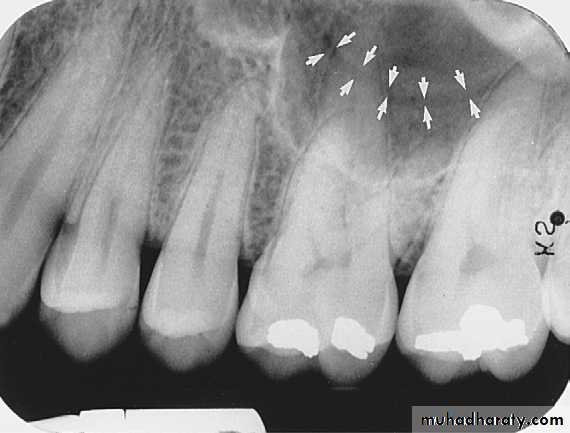

The maxillary sinus are paired cavities or compartments of bone located within the maxilla. The maxillary sinus are located above the maxillary permolars and molars teeth. Radiographically the sinus appears as a radiolucent area located above the apices of maxillary premolars and molars. The floor of sinus is composed of dense cortical bone and appear as radiopaque.

SEPTA WITHIN THE MAXILLARY SINUS:

Septa are bony wall that divided the maxillary sinus into compartment. Radiographically the septa appear as a radiopaque line within the sinus.

Nutrient Canals within Maxillary Sinus

Nutrient canals may be seen within maxillary sinuses. Nutrient canals are tiny, tubelike passageways through bone, which contain blood vessels and nerves that supply maxillary teeth and interdental areas. On a maxillary periapical image, a nutrient canal appears as a narrow radiolucent band bounded by two thin radiopaque lines.INVERTED Y